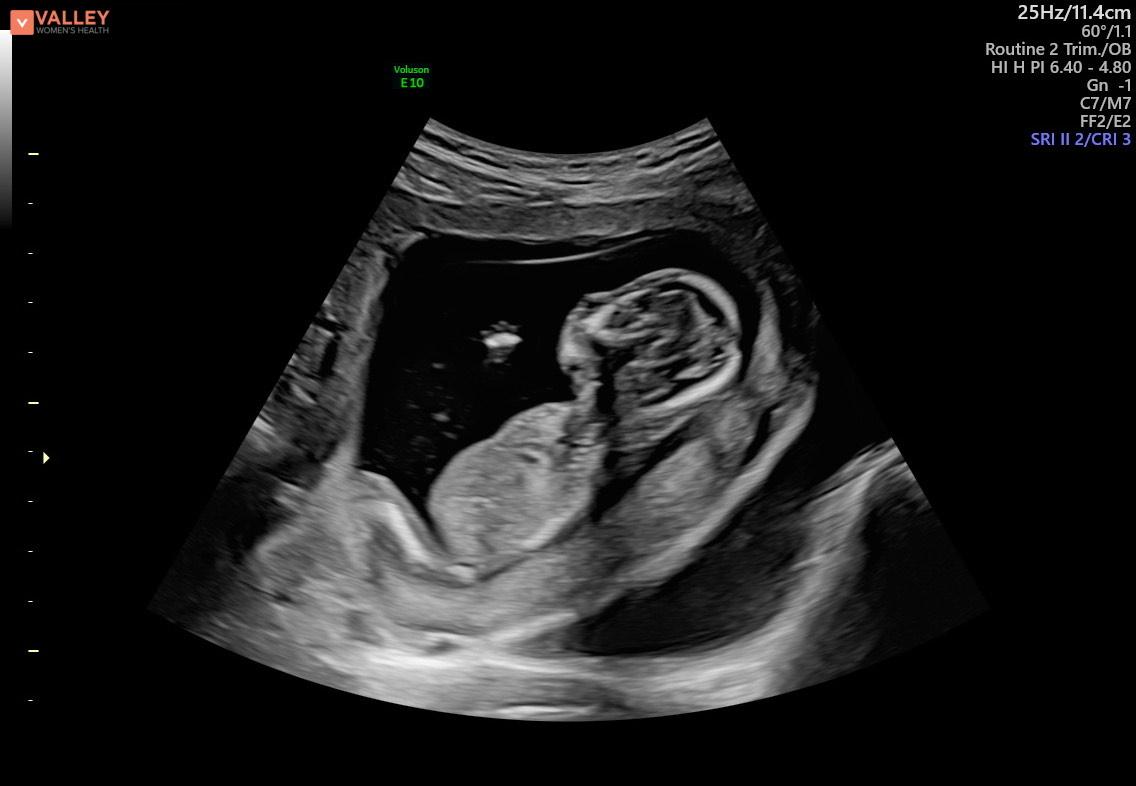

然而,在達到孕中期後,麥迪森開始有更多的發現。第二次超聲波檢查顯示她有另一個血腫,她孩子的大腦發育不正常。超聲技術人員也很難找到嬰兒的鼻骨。

在18週時,麥迪森最擔心的事情出現在母胎醫學掃描中,當時超聲技術人員在異常長的時間內保持沉默。

麥迪森的心開始跳動,因為她感到胃裡有一種下沉的感覺。沒過多久,醫生走進房間,給焦慮的父母做出了診斷:阿洛巴前腦無裂畸形 (HPE)——一種先天性疾病,嬰兒的大腦無法分為左半球和右半球。

這對夫婦得知嬰兒查理也患有多種心臟缺陷。醫生說,阿洛巴HPE的診斷是致命的。